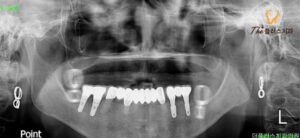

조금 더 정밀한 진단을 위해

파노라마 사진을 촬영해 보았더니

곳곳에 잔존 치근이 남아있었고

특히 상악에는 치아가 뿌리까지

충치에 이환되어 발치가 필요하였으며,

나머지 치아들도 치근이 짧아지고

치조골이 퇴축되어 흔들림이

심한 상태라 발치가 진행되어야 했습니다.

하지만 치아가 상실된 지 오래되어

잇몸이 수축되고 임플란트를 심기에는

상악동 거상술과 같은 부가적인 시술이

추가로 들어가야 안정적인

임플란트 식립이 이루어질 수 있었는데요.